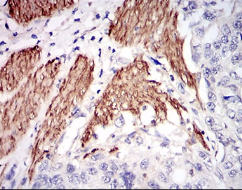

NPC1 Mouse Monoclonal antibody[8D10B]

IHC    1/200 - 1/1000